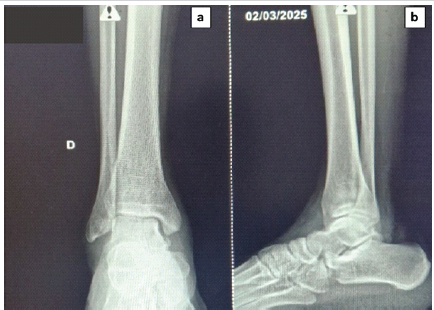

The ankle was immobilized in a below-knee plaster cast for 6 weeks without weight-bearing. Wound healing was achieved by day 12, and post-operative recovery was uneventful. The K-wires were removed at 6 weeks, followed by a structured rehabilitation program. At 6-month follow-up, the patient had regained a full range of motion in flexion and extension (Fig. 5), and control radiographs showed a congruent reduction with no signs of necrosis or degenerative changes (Fig. 6).

Figure 6: Follow-up radiographs at 6 months. (a) Standard anteroposterior and (b) lateral radiographs confirming maintained reduction and absence of secondary dislocation or post-traumatic osteoarthritis.